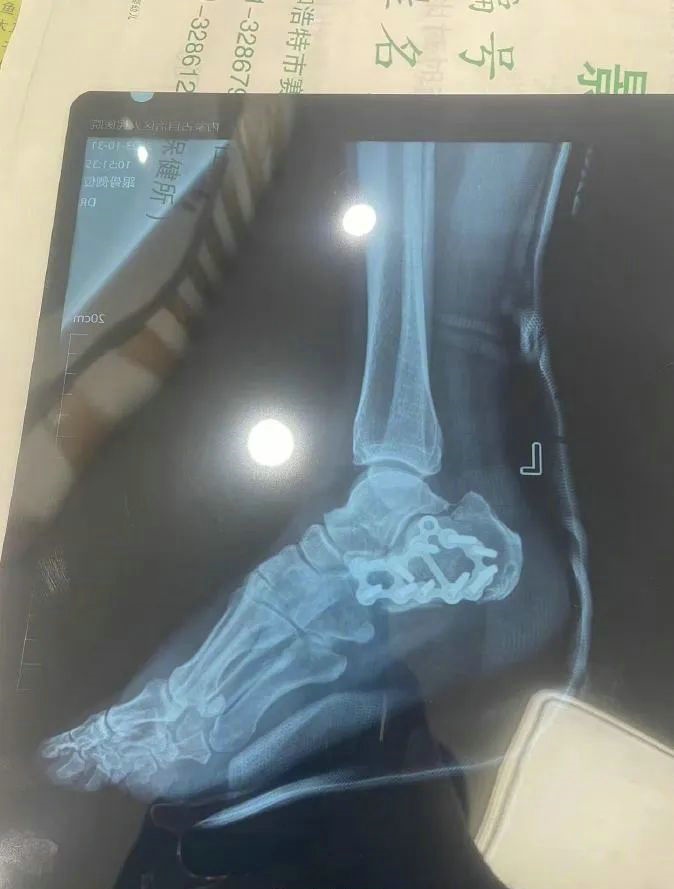

“那時(shí)候我剛工作了兩天,在第三天10月22日下午施工過(guò)程中從三層高的鐵架上摔了下來(lái),導(dǎo)致30厘米左右的鋼筋刺穿我的右側(cè)臀部,左腳跟也粉碎性骨折,被送往內(nèi)蒙古自治區(qū)人民醫(yī)院救治,當(dāng)晚做了手術(shù)取出刺在右臀部的鋼筋,10月30日又進(jìn)行了左腳粉碎性骨折手術(shù)?!崩紫壬嬖V記者。